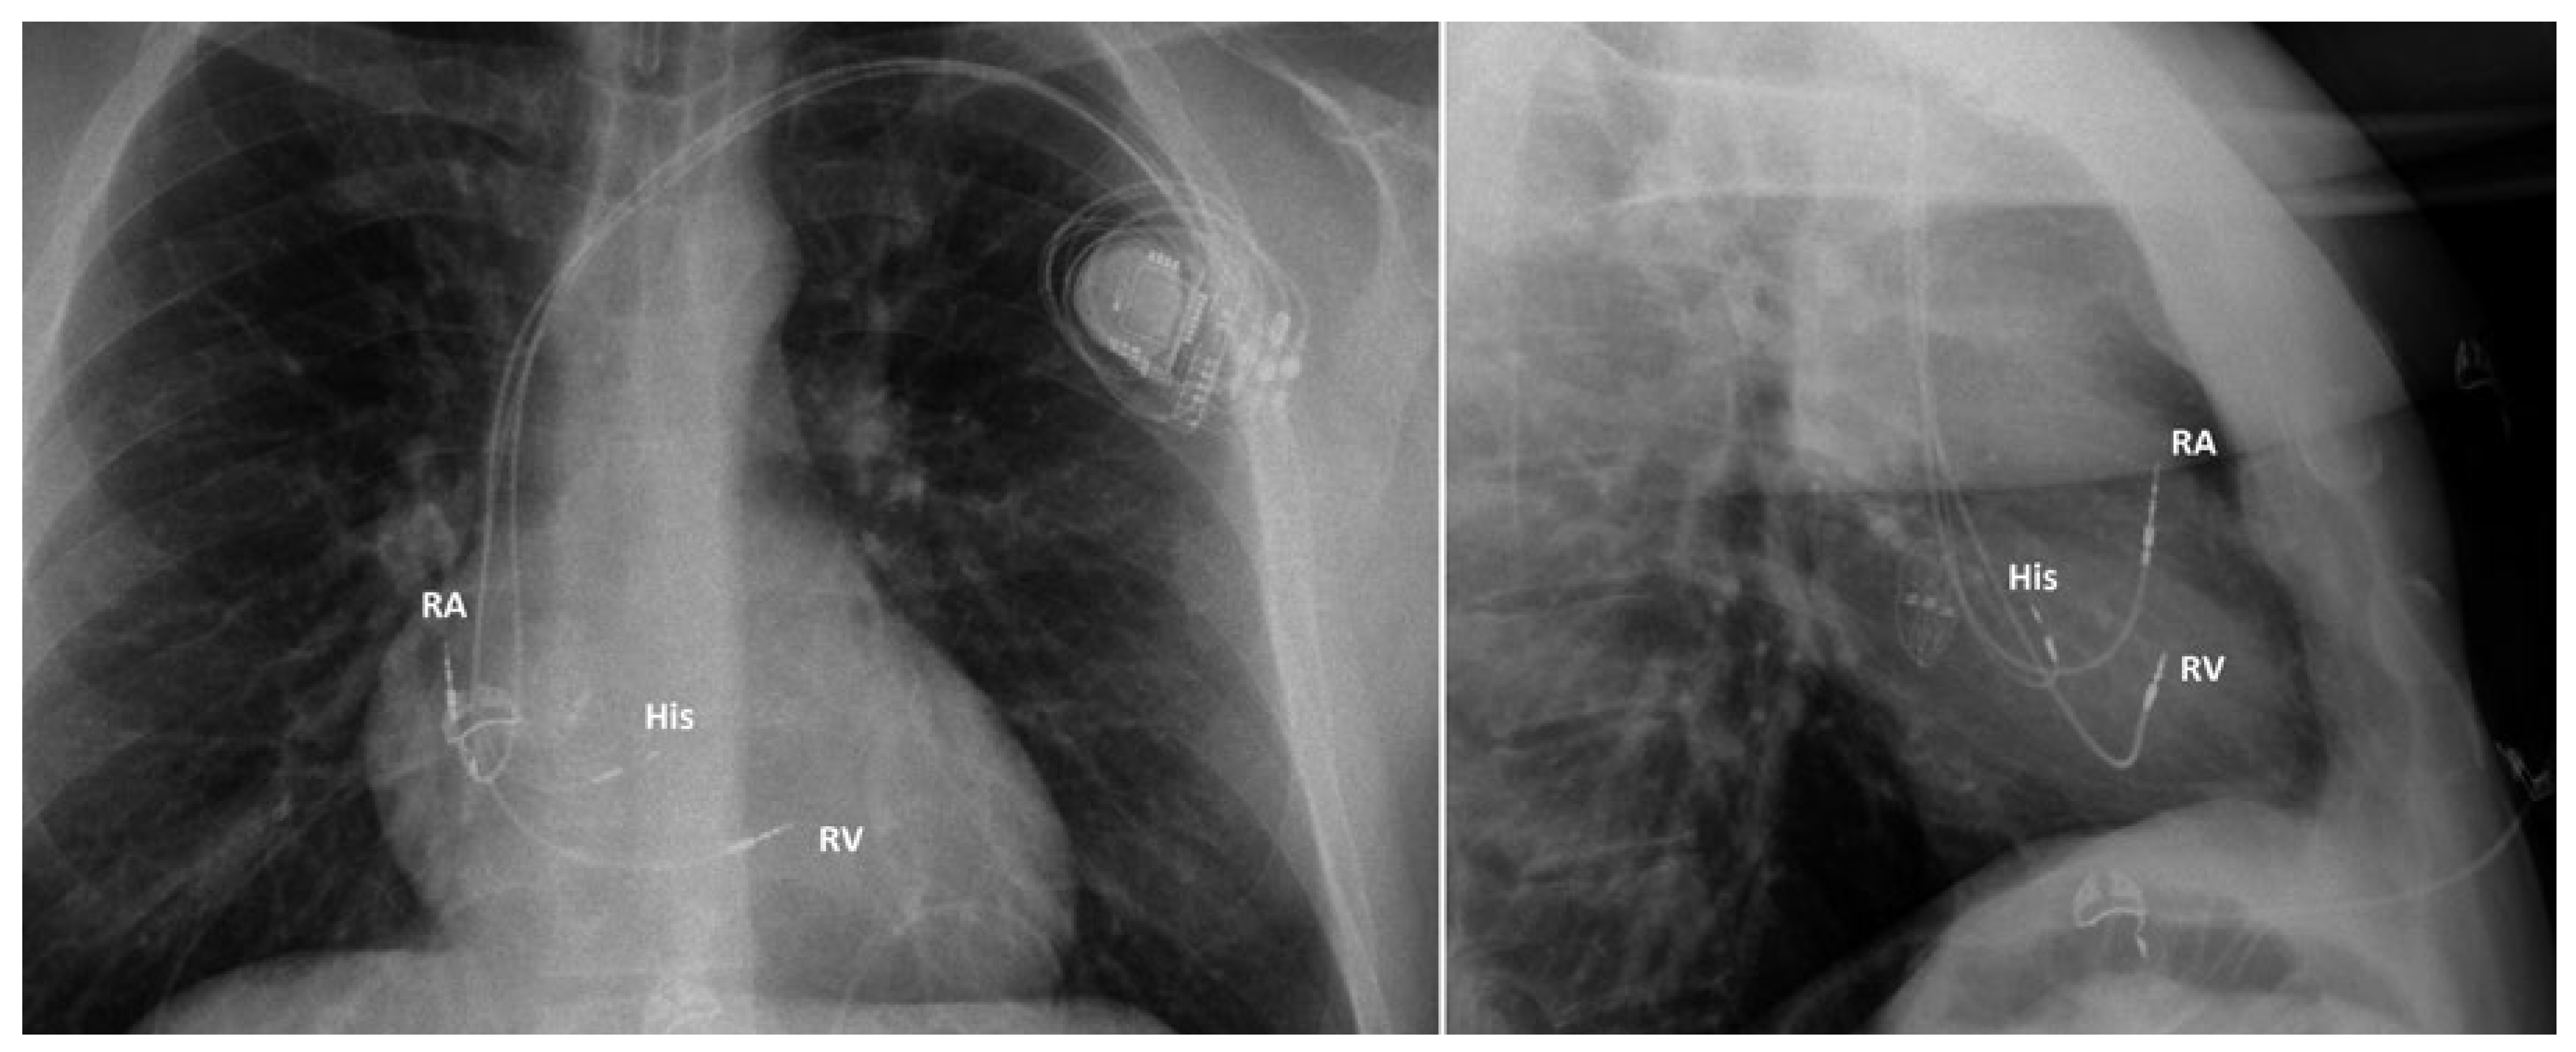

Figure 5. Chest X-ray in a patient implanted with a pacemaker for atrioventricular block. RA: right atrial lead; His: His bundle lead (connected to the left ventricular port of the biventricular pacemaker); RV: right ventricular lead on the interventricular septum (connected to the right ventricular port of the pacemaker).